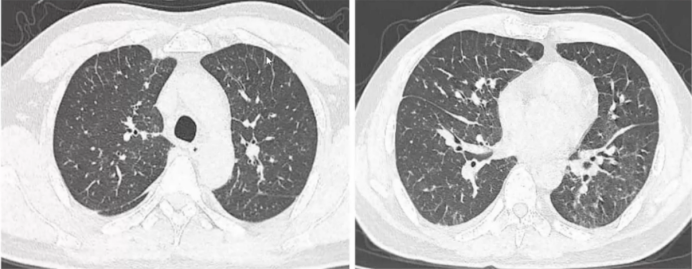

图片

1  低密度病灶、网格状病灶和高密度病灶表现